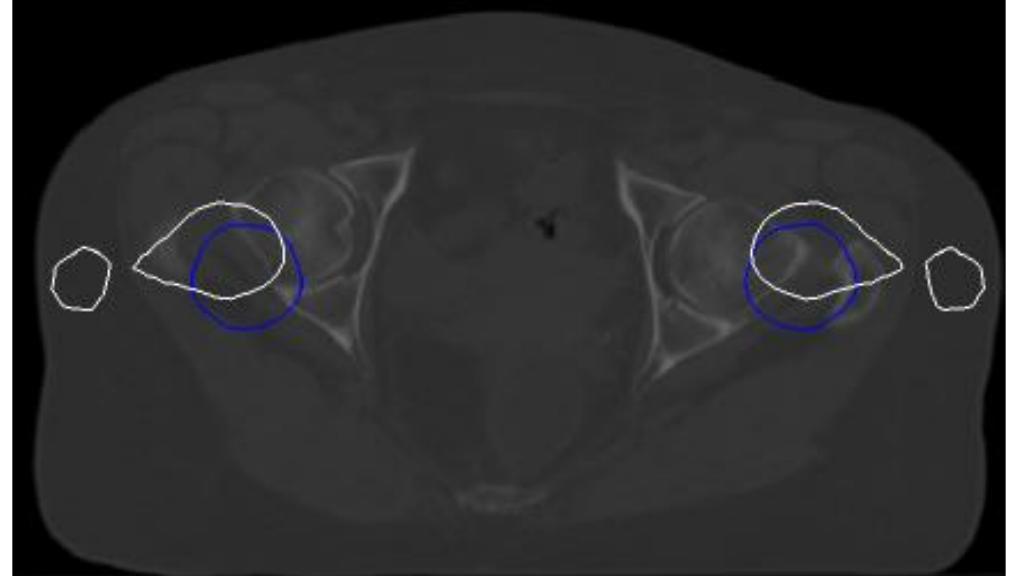

The article centers around using the You Only Look Once (YOLO) neural network during the time spent individual bones acknowledgment, in the arrangement of CT cuts of the human pelvic zone. The network was prepared on custom information,... more